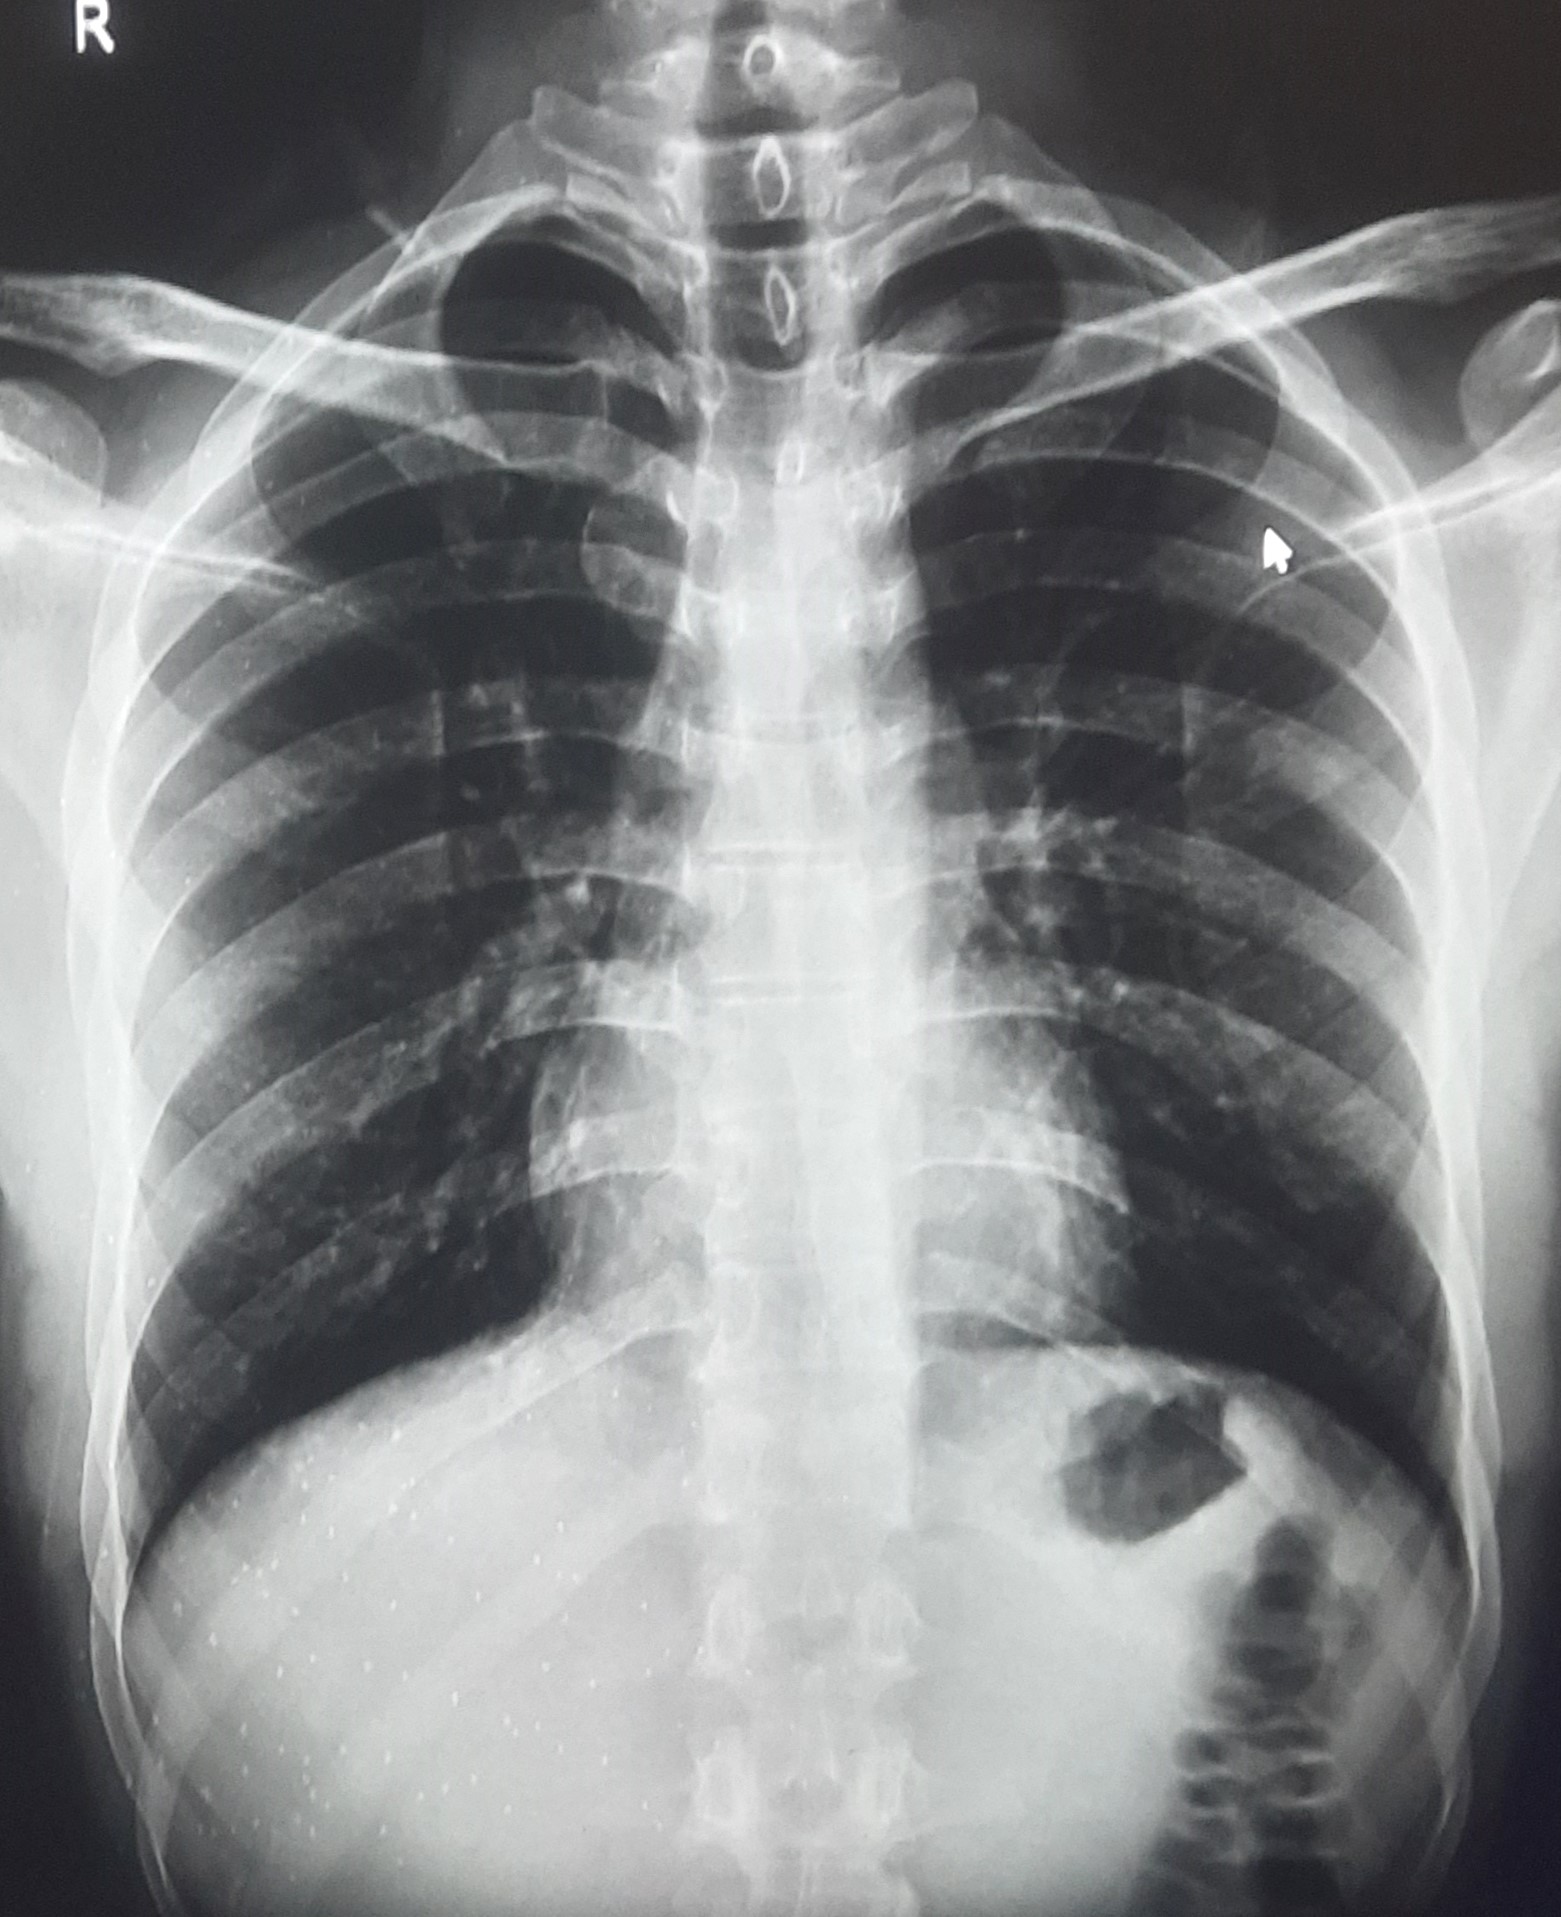

| 283 | IGGMC, Nagpur, Nagpur | P2 | 29-4189 Follow-up of 29-3923 |

Monali Pralhad Milmile | Consent taken on Paper | 46 Yrs. |

Provisional Diag : PTB Follow-up

Final Diag : Pleural Effusion |

TB Case (Confirmed) | Right Sided Upper Zone Fibrotic Lesion, Tracheal Pull Left side, Right sided & Left Sided Pleural Thickening Present, Right sided & Left Sided CP Angle Blunting Present, | Abnormality visible on x-ray |